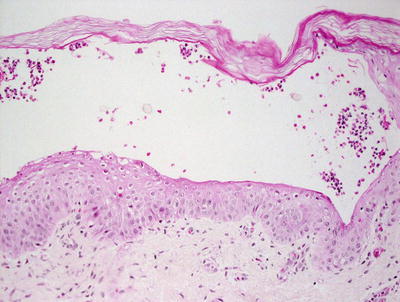

3.3.2 Histology

Histologic changes consist of a non-inflammatory subcorneal blister at the level of the granular layer (Fig. 3.7). In many cases, the stratum corneum, which is the blister roof, is desquamated and not present in the biopsy specimen. Its absence is often overlooked, making the diagnosis difficult. Rare acantholytic cells may be observed within the granular layer (Fig. 3.8). There is virtually no underlying inflammation within the dermis. Special stains for bacteria are negative [15].

Fig. 3.8

Rare acantholytic cells can be seen at the base of the separation in Staphylococcal scalded skin syndrome